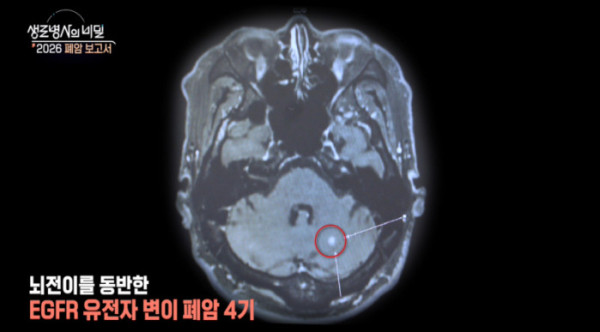

◆4기 암이 사라졌다? 암세포 흔적을 지운 완벽한 시너지

30년 동안 애연가로 살아온 강성원(65) 씨. 말이 어눌해지는 증상에 뇌출혈을 의심했지만, 진단 결과는 뜻밖에도 ‘폐암 4기’였다. 그러나 반전이 일어났다. 표적치료제와 수술의 시너지를 통해 현재 그는 몸속에서 암세포가 발견되지 않는 상태를 유지하고 있다. 기적 같은 상태, 어떻게 가능했을지 심층 취재한다.